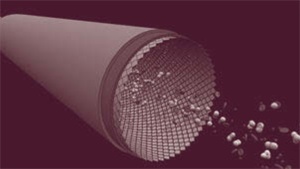

Рис. 3а

Рис. 3б

В ходе своих исследований доктор Эссельстин собрал новые доказательства того, что типичная западная диета, включающая переработанные масла, молочные и мясные продукты, разрушает клетки эндотелия, выстилающего изнутри стенки сосудов, и засоряет сосуды холестериновыми бляшками, которые препятствуют току крови. На рис. 3а показан кровеносный сосуд с бляшками, на рис. 3б – кровеносный сосуд человека, питающегося только продуктами растительного происхождения